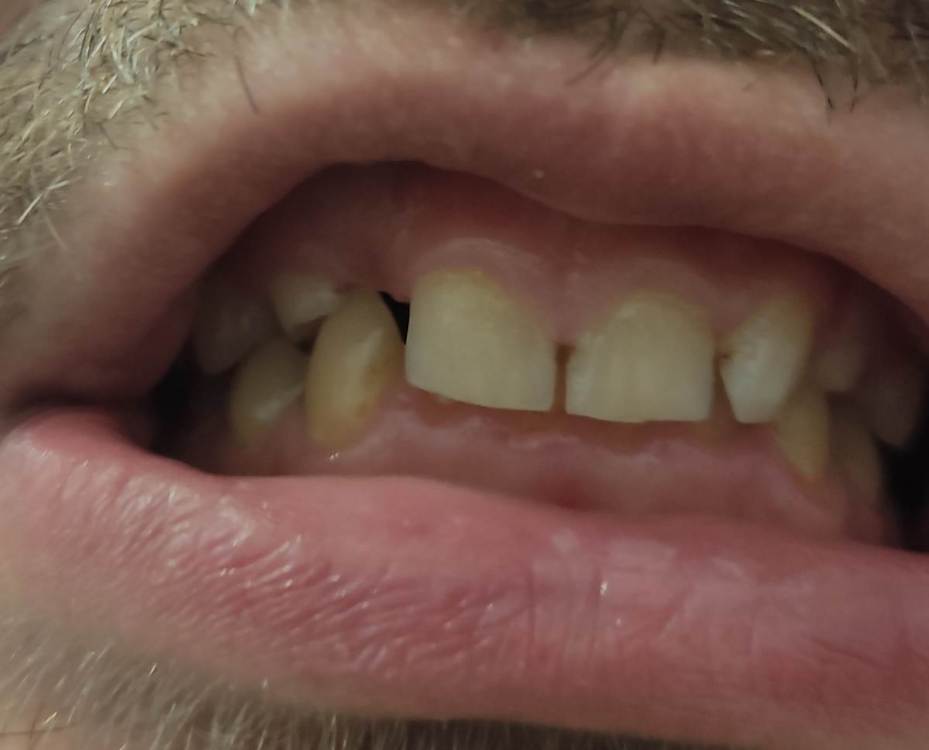

smikvarnik Опубликовано 12 июня, 2023 Поделиться Опубликовано 12 июня, 2023 (изменено) Здравствуйте, проблема следующая 25 лет, пол М У меня с детства аномалии(нет корней на 3х зубах), одна двойка справа молочная + тройки молочные. Двойка выпала и хожу с дыркой уже лет 10, также зона улыбки кривовата и есть промежуток между однерками тройки молочные маленькие но держатся, все хорошо. Самая главная проблема по которой мне многие отказывали в реставрации только зоны улыбки, это прикус. у меня глубокий прикус с детства. Ортодонты говорят что нужно носить брекеты 2-3 года, и только после этого имплантация либо коронки с мостами. Но пару ортопедов предложили мне сточить все верхние зубы(все жевательные зубы в отличном состоянии, передние так себе, уже немного сточены из за прикуса). Говорят что если поставить без исправления прикуса - я просто выбью коронки или импланты, нагрузка будет не такая какая должна быть Пробовал также ходить с капой чтобы поднять прикус - результатов нет. некоторые врачи отказывали даже в лечении брекетами, говоря что ситуация сложная. Также зубы для моего возраста маленькие, по сравнению с другими людьми Говорят что если сделать коронки на верхней челюсти, можно таким образом исправить прикус+сделать улыбку без ортодонтии. но также возможно потребуется сточить немного зубов на нижней(не уточнял какие) Коронки из диоксида циркония как вы считаете, это нормальный вариант, или так себе? у меня психологический комплекс из за зубов и еще 2-3 года ходить с брекетами и дырками честно говоря так себе идея. Какие есть минусы и опасности у такого варианта, и как с вашей точки зрения, как докторов, этот вариант оценивается? Насколько это целесообразно? Спасибо за помощь заранее, очень жду ответ, каждый день волнует эта тема Изменено 12 июня, 2023 пользователем smikvarnik Ссылка на комментарий

smikvarnik Опубликовано 13 июня, 2023 Автор Поделиться Опубликовано 13 июня, 2023 также ситуация во рту, и с прикусом. молочные зубы выделил. извините за флуд) Ссылка на комментарий